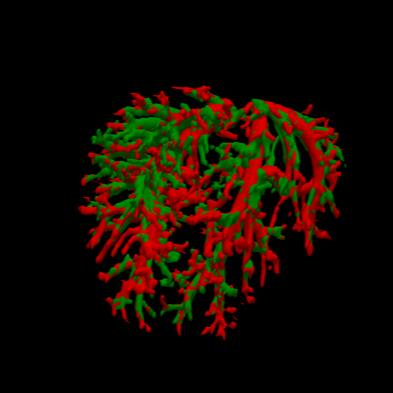

Manually segmenting the hepatic vessels from Computer Tomography (CT) is far more expertise-demanding and laborious than other structures due to the low-contrast and complex morphology of vessels, resulting in the extreme lack of high-quality labeled data. Without sufficient high-quality annotations, the usual data-driven learning-based approaches struggle with deficient training. On the other hand, directly introducing additional data with low-quality annotations may confuse the network, leading to undesirable performance degradation. To address this issue, we propose a novel mean-teacher-assisted confident learning framework to robustly exploit the noisy labeled data for the challenging hepatic vessel segmentation task. Specifically, with the adapted confident learning assisted by a third party, i.e., the weight-averaged teacher model, the noisy labels in the additional low-quality dataset can be transformed from "encumbrance" to "treasure" via progressive pixel-wise soft-correction, thus providing productive guidance. Extensive experiments using two public datasets demonstrate the superiority of the proposed framework as well as the effectiveness of each component.

翻译:将来自计算机地形学(CT)的肝脏船只人工分割,由于船只的低调和复杂形态,由于低调和复杂的形态,造成极端缺乏高质量的标签数据,因此比其他结构更需要专门知识和难度大得多。如果没有足够的高质量的说明,通常的数据驱动的基于学习的方法就会与不足的培训斗争。另一方面,直接引进低质量说明的额外数据可能会混淆网络,导致不良的性能退化。为了解决这一问题,我们提议建立一个新的、由教师协助的、有说服力的、有说服力的学习框架,为具有挑战性的肝脏船只分解任务强有力地利用响亮的标签数据。具体地说,在第三方(即加权平均教师模式)的协助下,经过变通的自信学习后,额外低质量数据集中的噪音标签可以从“阻力”转变为“压力”,通过渐进式的像素方法的软校正,从而提供富有成效的指导。使用两个公共数据集进行的广泛实验,显示了拟议框架的优越性以及每个组成部分的效能。